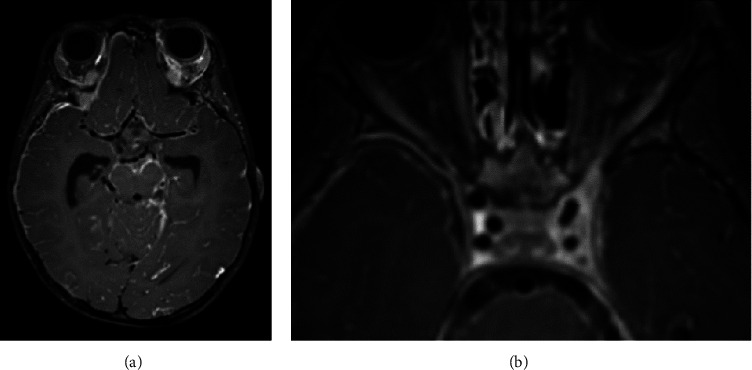

Abstract Image